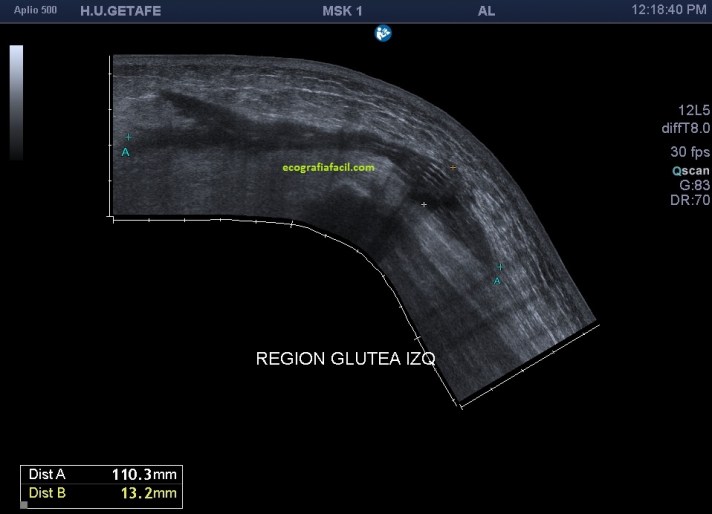

Es lo que ves en este otro caso, imagen 4, 5 y 6, donde se observan estos cambios que has visto en la primera parte de Post, pero además, aquí el caso es diferente, la etiología es distinta y en este caso, la paciente presentaba cambios en partes blandas y un gran absceso infeccioso en profundidad que requirió colocación de un drenaje.

El absceso era de tal calibre que debí usar vista panorámica (imagen 4) que evidenció una medida máxima de 11 cms, si no tienes este ajuste, puedes usar la sonda de baja frecuencia, que tiene peor calidad de imagen, pero permite medidas grandes (imagen 5).

4